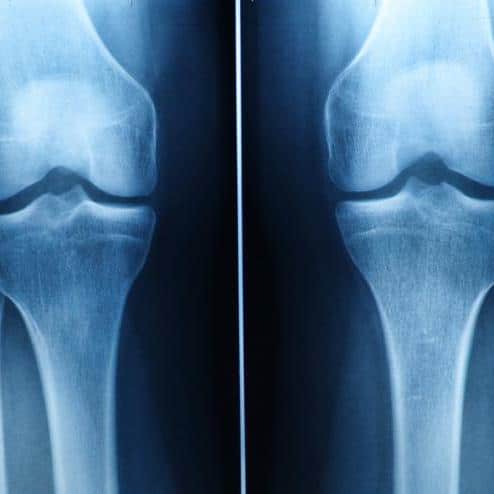

Can Stem Cells treatment Regrow the knee cartilage?

Some people believe that stem cells can achieve this, but studies show it's unlikely in most cases. While minimal growth…